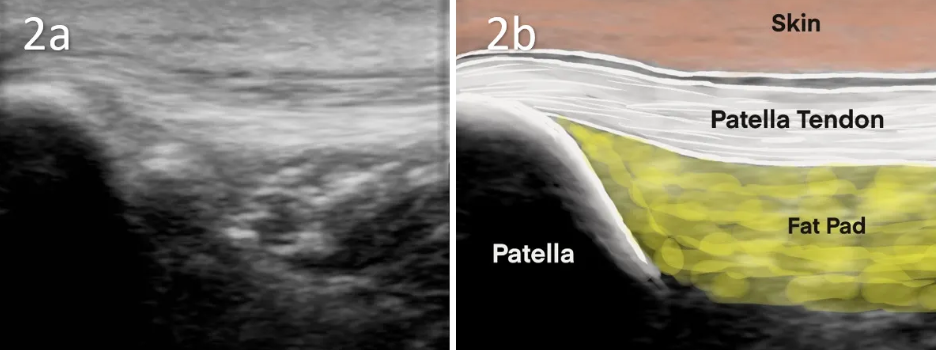

- 호파 지방패드(Hoffa's Fat Pad)

- 위치: 슬개건 후방, 관절 내 위치

- 기능: 충격 흡수, 활액 분비 보조

- 신경 분포: 풍부한 감각 신경 말단 (통각 민감)

해부학 및 병리생리학

호파 지방패드의 기능:

- 충격 흡수: 무릎 신전 시 대퇴골과 경골 사이 완충

- 활액 분비: 관절 윤활 보조

- 공간 충전: 관절 내 빈 공간 채움

신경 분포:

- 매우 풍부한 감각 신경 말단

- 통각에 매우 민감

- 슬개하 신경(infrapatellar nerve) 분지 통과